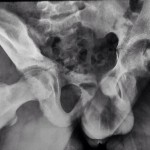

Courtesy: Lalit Maini, New Delhi

Case Study: Paediatric #Hip